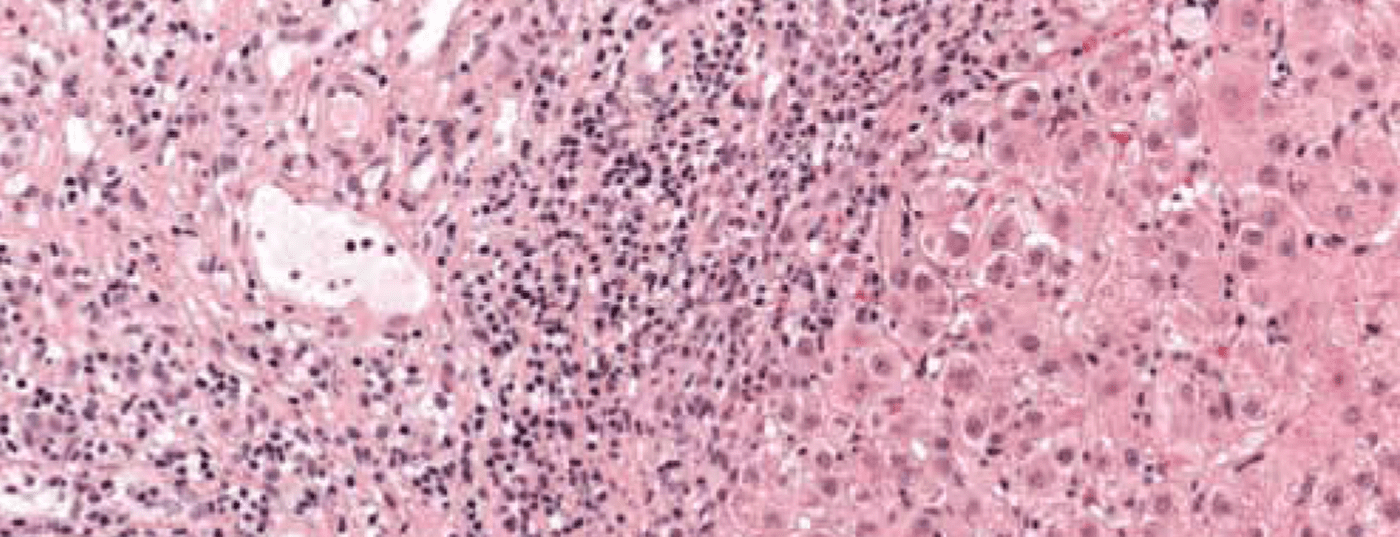

• Autoimmunhepatitis

Die Autoimmunhepatitis (AIH) ist eine chronische, progressive Lebererkrankung, die durch das histologische Bild einer Interfacehepatitis, einer Hypergammaglobulinämie und zirkulierende Autoantikörper charakterisiert ist. Die AIH tritt in allen Altersgruppen auf und...…